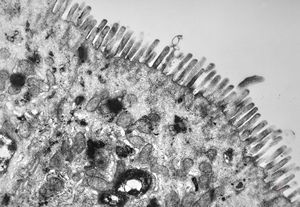

normal mucosa - jejunum - microvilli(anchored core rootlets)

normal mucosa - jejunum - microvilli